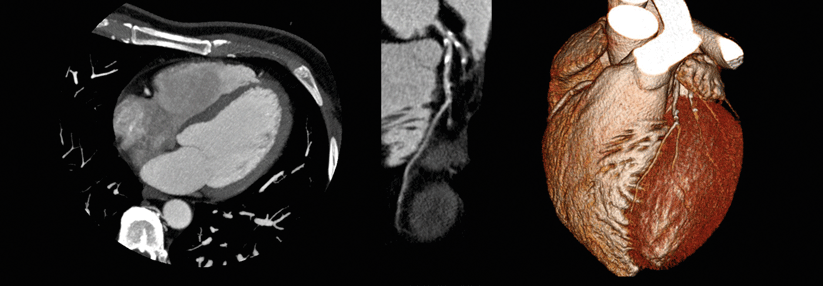

Insgesamt werteten sie die Ergebnisse der Angiographie und der optischen Kohärenztomographie (OCT) von 105 Patienten aus (81 % Männer, 70 % mit Statintherapie). Die durchschnittlich 68-jährigen Teilnehmer hatte man im Rahmen einer diagnostischen Koronarangiographie bzw. einer perkutanen Koronarintervention untersucht. Über die OCT-Aufnahmen ließen sich atherosklerotische Gefäßveränderungen darstellen und abgeheilte Läsionen identifizieren.